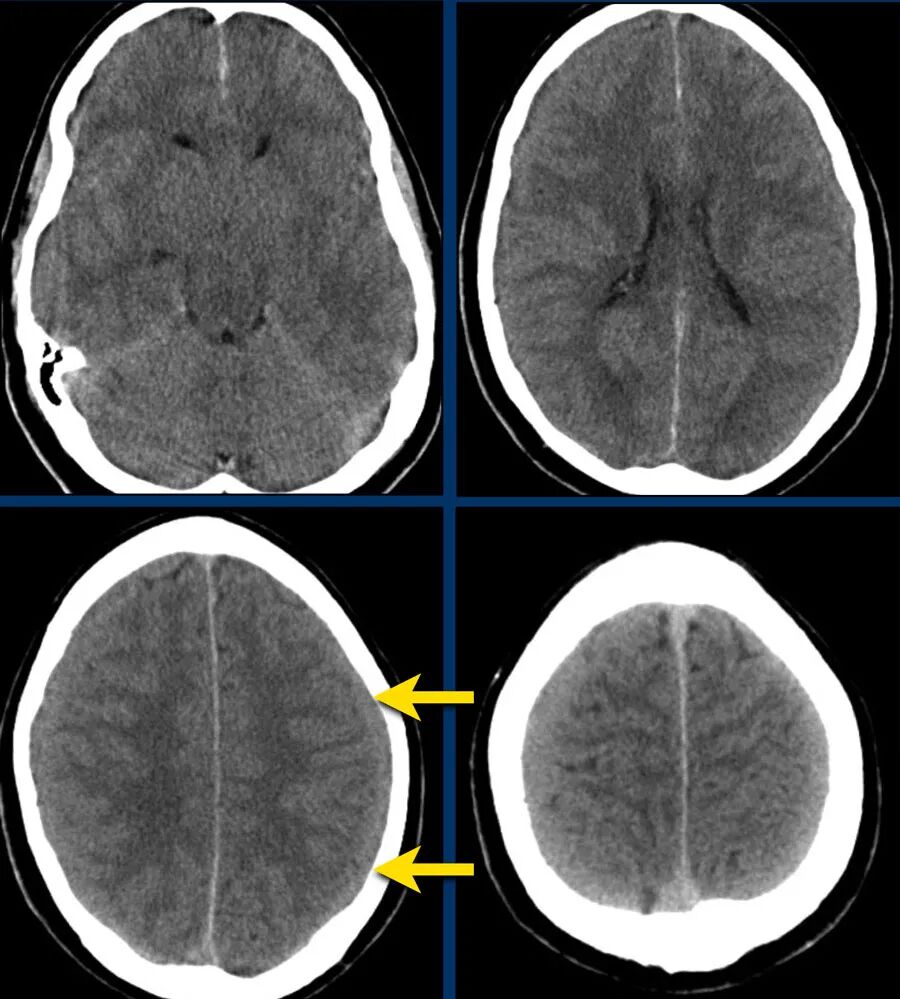

下图显示了外侧裂蛛网膜下腔(黄色箭头)的高密度血液。

注意右侧枕部的皮下出血(蓝色箭头)。

这是一种对冲伤。